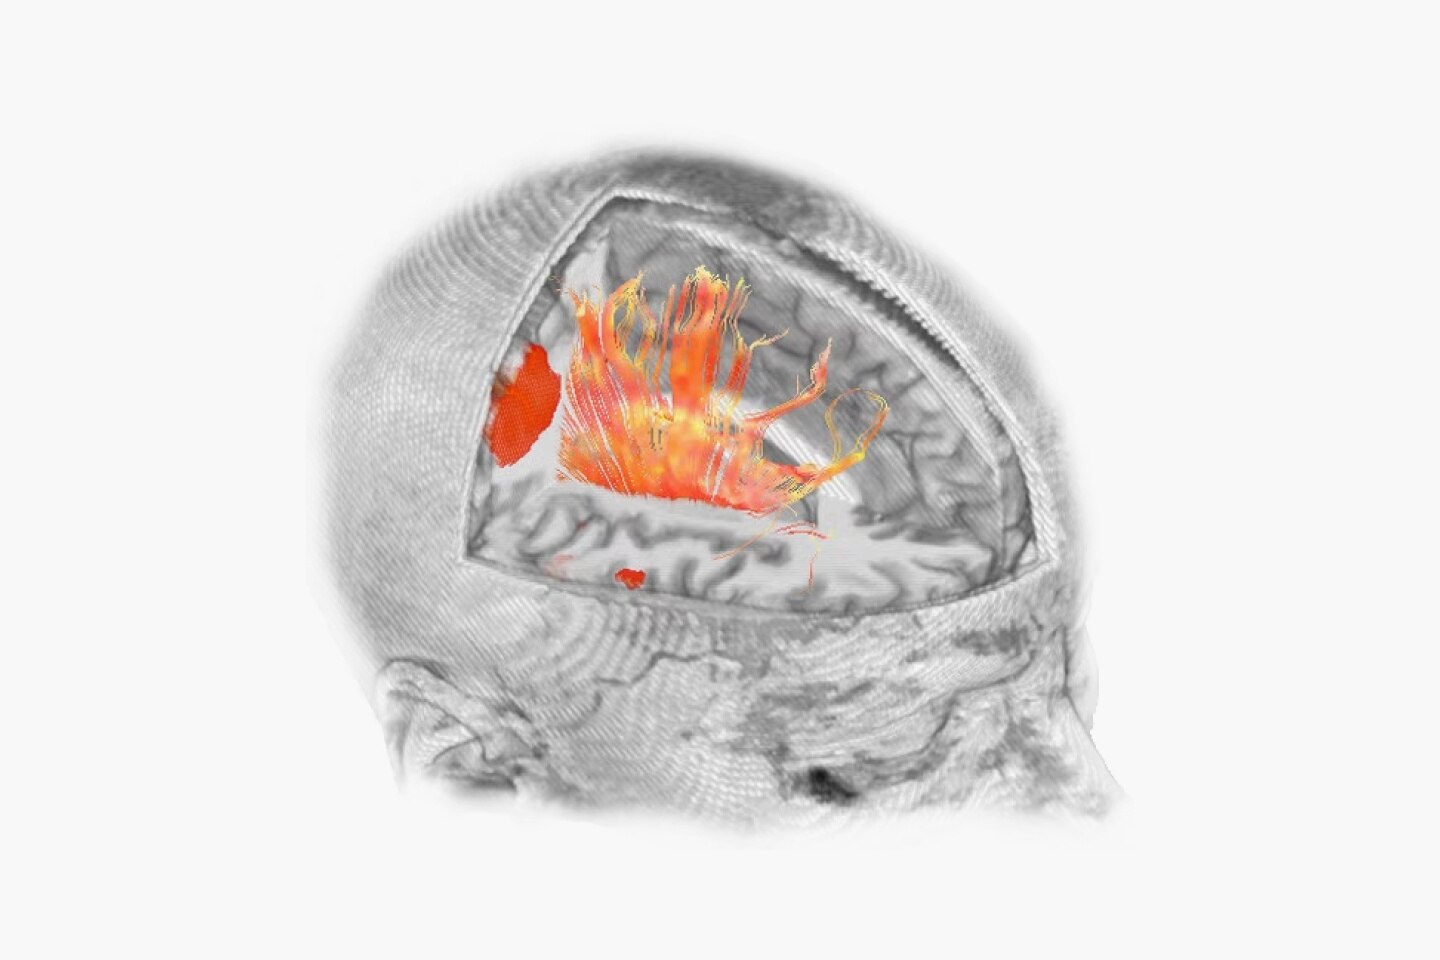

Discover the advanced capabilities of the SIGNA™ Architect, GE HealthCare's 3T magnet MRI system. Featuring a 128-channel Total Digital Imaging (TDI) receive chain and exceptional 44mT/m @ 200T/m/s gradient performance, this system sets a high standard for precision. Streamline your workflow effortlessly with products like AIR™ Recon DL, AIR™ Coils, and Sonic DL™, designed to enhance your diagnostic efficiency.

Reinforce your clinical confidence with the SIGNA™ Architect's AI-based applications, powered by Edison. Implement feet-first imaging for all exams, emphasizing a patient-friendly approach. The Effortless AIR™ Recon DL further enhances imaging efficiency, providing diagnostic precision to meet your high standards.